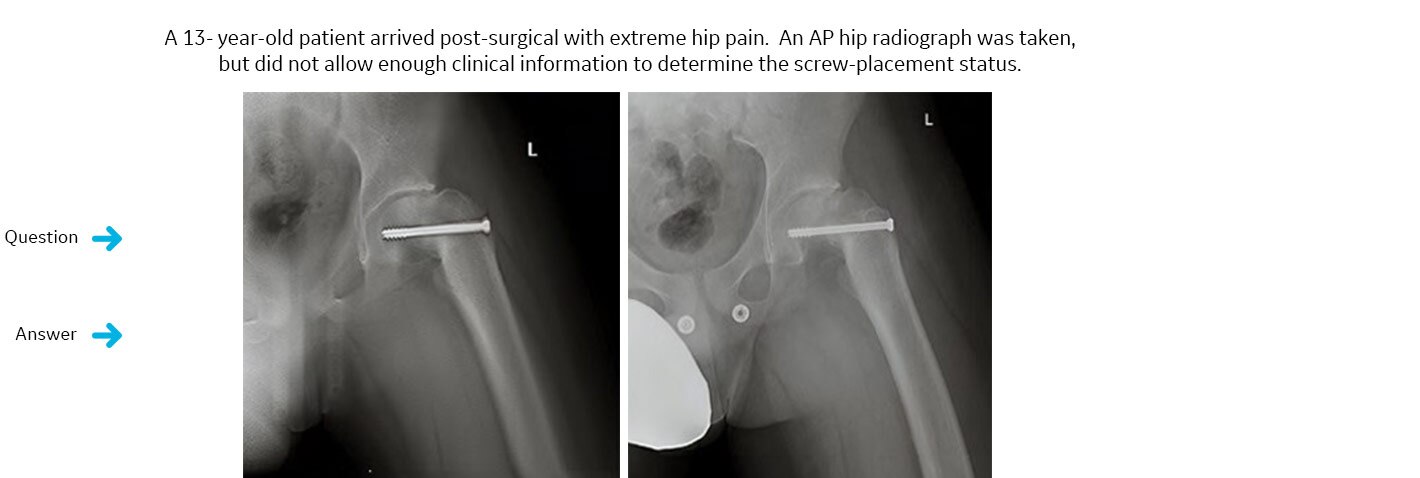

¿Ha invadido un tornillo implantado el espacio de la articulación de la cadera?

Se solicitó un estudio VolumeRAD. VolumeRAD permite la eliminación de estructuras superpuestas y ayuda a realizar un diagnóstico fiable.La respuesta definitiva: no.

Un intervalo de un solo corte de los datos de VolumeRAD reveló que el tornillo implantado no había invadido el espacio articular. El paciente se sometió a una intervención quirúrgica secundaria y se confirmó la correcta colocación del implante.